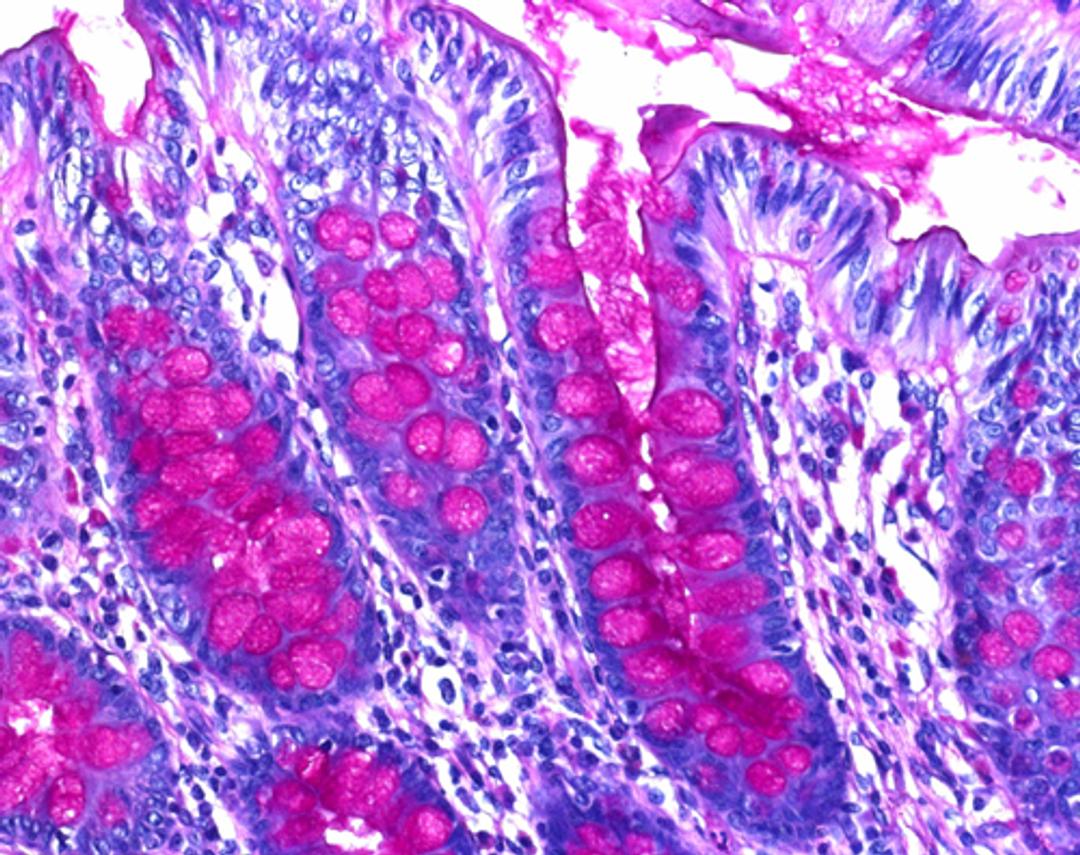

Schiff’s reagent Intense - for the detection of aldehyde and mucosubstances in microscopy” is used for human-medical cell diagnosis and serves the histological investigation of sample material of human origin. It is a ready-to-use staining solution that when used together with other in vitro diagnostic products from our portfolio makes target structures (by fi xing, embedding, staining, counterstaining, mounting) in human-histological specimen material, for example histological sections of e.g. the intestine or liver, evaluable for diagnostic purposes.